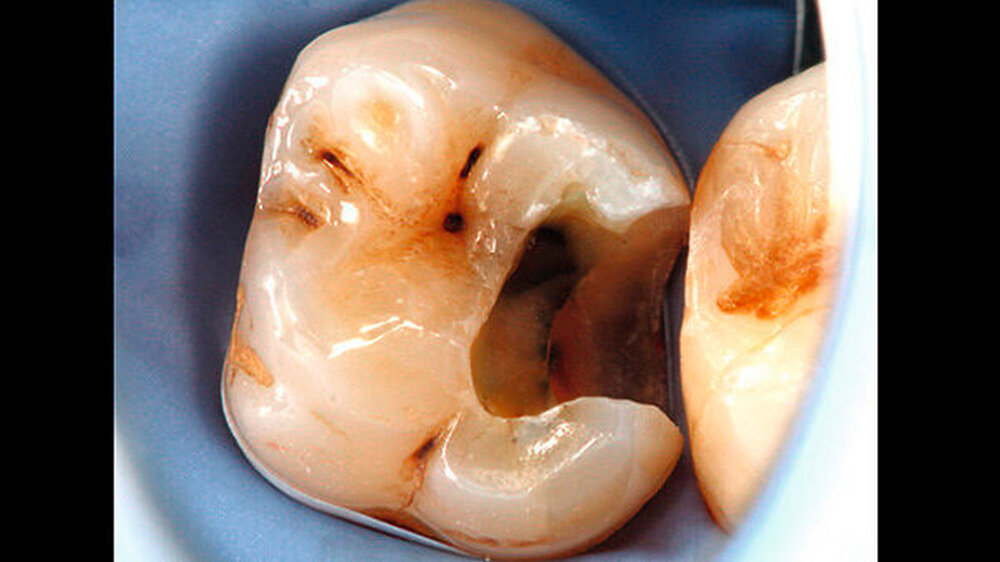

Das Zementmaterial wurde nach Herstellerangaben angemischt und mittels eines kleinen Kugelstopfers (Dycal-Instrument) im Bereich der distalen pulpalen Wand appliziert und mit einem Heidemann-Spatel adaptiert. Das Material wurde damit gleichzeitig sowohl zur Caries-profunda-Behandlung als auch zur Unterfüllung eingesetzt. Nach einer Abbindezeit für das Material von zwölf Minuten wurde der Defekt mit einer Kompositfüllung restauriert (Abbildung 4).

Zur Füllungstherapie wurde ein Etch&Rinse-Adhäsiv (ExciTE, Ivoclar Vivadent) in Kombination mit einem Feinpartikelhybridkomposit (Tetric EvoCeram, Ivoclar Vivadent) verwendet. Nach Anätzen des Schmelzes mit Phosphorsäure (Total Etch, Ivoclar Vivadent) (Abbildung 5) und Applikation des Adhäsivs (ExciTE DC, Ivoclar Vivadent) (Abbildung 6) wurde zunächst eine erste Schicht aus einem opaken, fließfähigen Komposit in die Kavität eingebracht (Venus Flow Baseliner, Heraeus Kulzer).

Das Kavitätenlining mit einem Flowkomposit ermöglicht eine gute Primäradaptation und stabilisiert den Haftverbund zum Dentin beim Einsetzen der Polymerisationsschrumpfung des nachfolgend platzierten Komposits [Haller B, 2009]. Zudem ermöglicht der opake Liner eine Abgrenzung des Übergangs zur natürlichen Zahnhartsubstanz (Abbildung 7).

Anschließend erfolgte der Aufbau der Restauration in Inkrement-Technik. Nachdem der Kofferdam entfernt wurde, wurden Okklusion und Artikulation überprüft, und es erfolgten Ausarbeitung und Politur (Abbildung 8) mit Feinkorndiamanten.